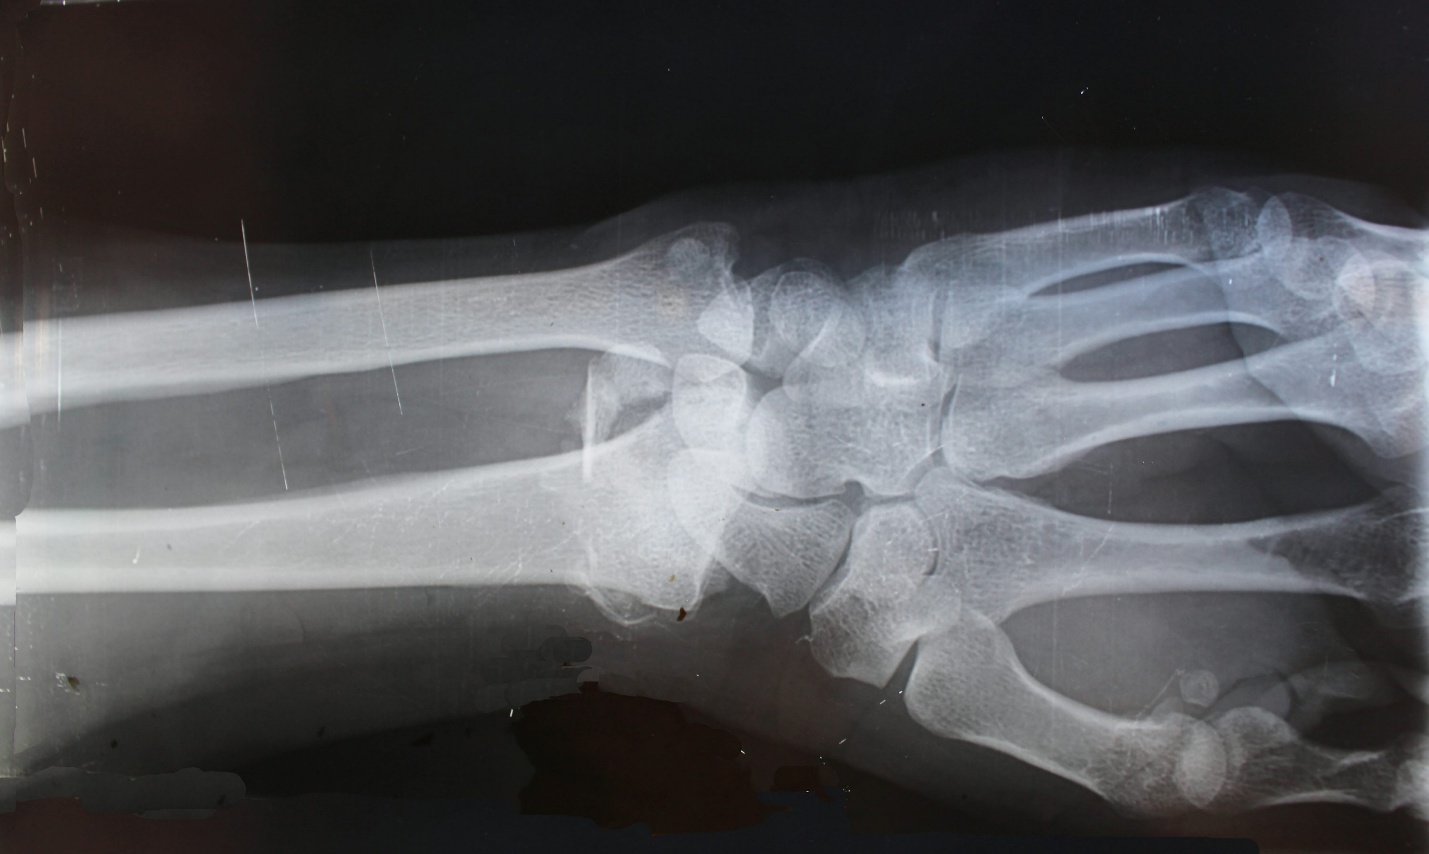

Certain symptoms suggest more than a simple sprain or strain. Rapid swelling, visible deformity, inability to bear weight, numbness, or a popping sensation at the time of injury indicate possible ligament rupture or fracture. Severe pain that does not improve after several days of rest also warrants assessment.

The Centers for Disease Control and Prevention notes that falls remain a leading cause of injury nationwide. While many fall-related injuries are minor, fractures and significant ligament tears do occur. Imaging, such as X-rays or MRI scans, may be necessary to clarify the severity.